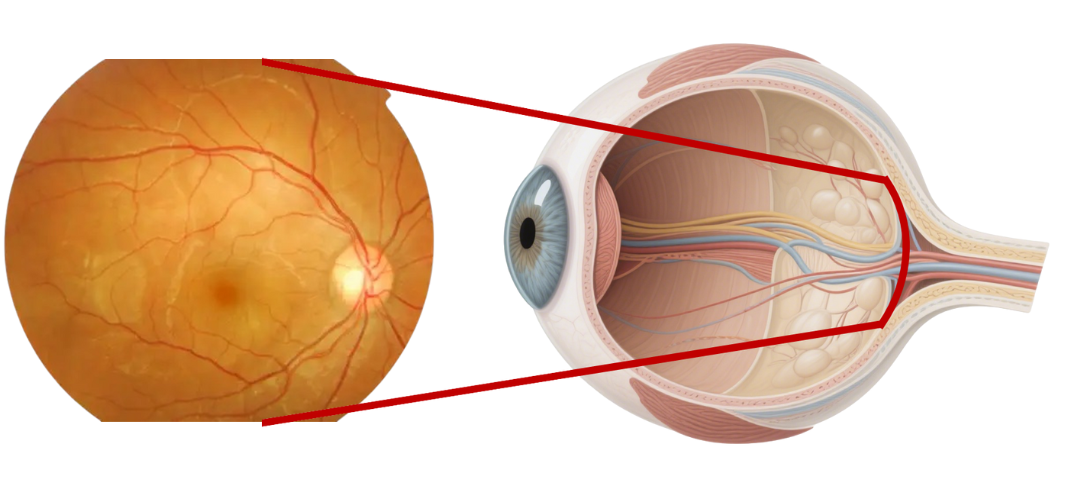

Optical Fundus Camera Get Retinal Layer

Traditional optical fundus cameras have a small field of view, generally 40 to 60 degrees, and can only see the retinal layer of the fundus, but cannot obtain a complete fundus image.

Scanning Laser Ophthalmoscope Obtain Retinal Layer and Choroidal Layer

Our scanning laser ophthalmoscope uses multi-wavelength laser scanning to penetrate the fundus, capture details of the retinal and choroidal layers, and obtain high-definition fundus images.